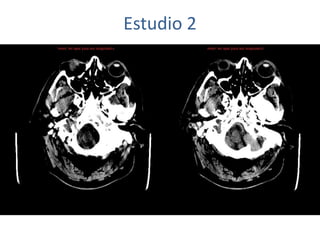

Estudio 2

• Estudio sin y con contraste, con reconstrucciones sagitales y coronales

del estudio con contraste.

Se observa una lesión ocupante de espacio en lóbulo frontal derecho que

presenta un tamaño de 18 x 32 x 22 mm (cc x ap x tr), bilobulada, no del

todo bien delimitada, con realce en anillo irregular, con hipocaptación

central, probablemente por necrosis, y asociada a un extenso edema

vasogénico con efecto masa tanto sobre los surcos de la convexidad

como sobre la cisterna insular, el sistema ventricular y la línea media,

esta última con un desplazamiento de 5 mm a la altura del septo

interventricular.

No se aprecian otras lesiones focales intra o extraaxiales de significación

patológica.

Habría que considerar como primera posibilidad que se tratase de una

lesión metastásica, por bien un tumor primario, aunque no se puede

descartar otras opciones, sin imprescindible correlación con la clínica y

con sus antecedentes.